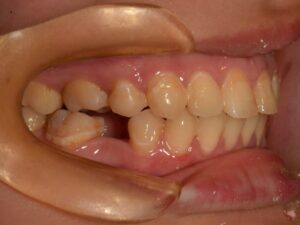

ただ

難しい 症例 です ので

上顎 は 完璧 なん です

下顎 に 少し 【スペース】が 生じました。

ご覧 の 通り

スペース が 狭すぎる の です。

決して インプラント治療が デキない 訳では ありません。

完成した クラウン修復 は 【違和感】 ある くらい

小さな 【歯】に なって しまいます。